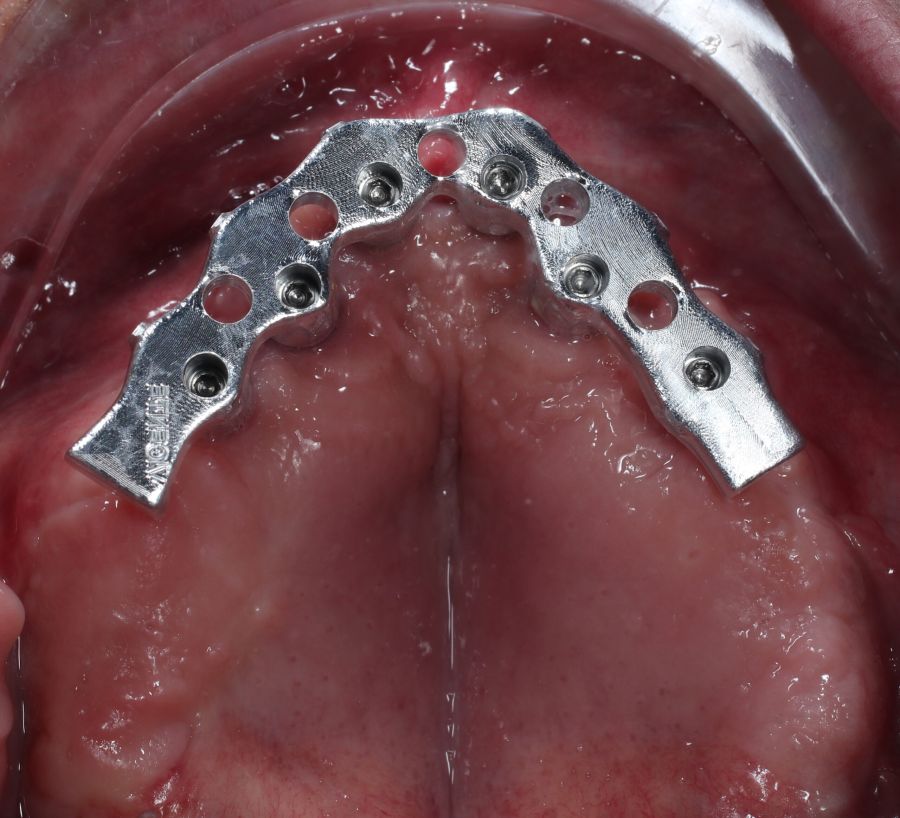

The surgical procedure was performed under general anaesthesia and nasotracheal intubation. A supracrestal incision and detachment of a maxillary flap of total thickness was made (Figures 9 and 10). The boundaries of the dissection were both infraorbital ridges, both laterally malar bodies and the anterior half of the hard palate caudally. In addition, a customized cutting guide was used so that the SI was completely in direct contact with the bone (Figure 11) and the mesh was fixed with the different 1.5 mm osteosynthesis screws in the nasal and zygomatic buttresses (KLS Martin, Freiburg, Germany) (Figure 12). The closure was performed with nonresorbable suture. Finally, the PMMA provisional rehabilitation was screwed for the immediate load, with a torque of 20 N on the implants (Figures 13-15).

Two months later, with the soft tissues healed around the connections (Figure 16), a new intraoral scanning was made of the implants and the provisional prosthesis for future restoration. A FRI type passivity test (rigid impression splint) was manufactured with an aluminium structure to assess the correct fit on the implants (Figure 17). For implant-supported rehabilitation, a sintered structure was made in chrome-cobalt with machined bases covered with acrylic resin teeth from Bredent® (Figures 18-21).